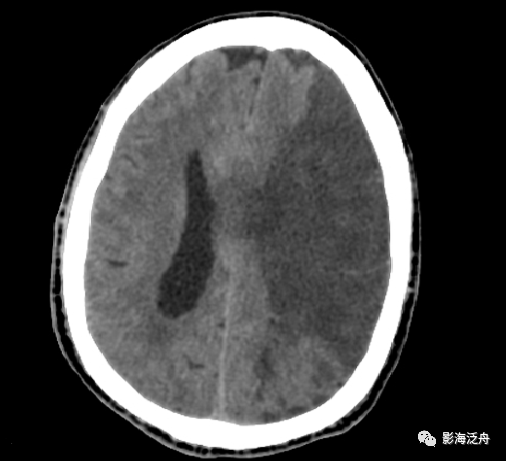

头颅ct平扫(术后第2日):左侧额叶及基底节区脑梗死(与前1日影像对比